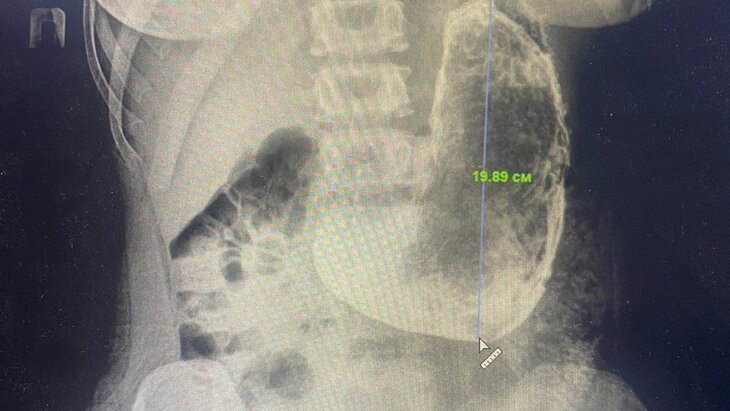

Новости здравоохраненияВ Красногорске врачи удалили девушке 20-сантиметровый желудочный камень

В результате проведенного обследования врачи подмосковного медучреждения обнаружили в просвете желудка пациентки безоар, размер которого составлял 20 на 15 сантиметров.